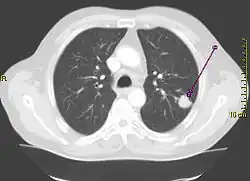

Рентгенограмма грудной клетки, демонстрирующая солитарный лёгочный узел в верхней доле левого лёгкого. | |

Солитарный лёгочный узел (одиночное периферическое образование) — в рентгенологии, периферическое образование в лёгочной ткани размером менее 3 см. Может быть случайной находкой на 0,2 % рентгенограмм грудной клетки[1] и около 1 % компьютерных томограмм[2].

Солитарные лёгочные узлы следует отличать от инфильтратов, более крупных опухолей или образований с иными сопутствующими радиологическими симптомами. Солитарный лёгочный узел представляет собой единичный периферический очаг, со всех сторон окружённый лёгочной тканью, диаметром менее 3 см, не ассоциированный с пневмонией, ателектазом или лимфаденопатией[3][4].

Дифференцировать злокачественное периферическое образование от доброкачественного помогают некоторые особенности. Учитывается размер образования: чем оно меньше, тем меньше риск злокачественности. Доброкачественные образования обычно имеют чёткие контуры, злокачественные имеют неравномерные, местами нечёткие границы или дольчатую структуру[4]. При наличии в образовании полости имеет значение толщина её стенок: чем тоньше стенка, тем более вероятна его доброкачественная природа и наоборот (наиболее достоверна толщина стенок менее 4 мм или более 16 мм, соответственно)[4]. При раке лёгкого полость в толще очага обусловлена некрозом (распадом) или вторичным абсцедированием. Если на фоне очага визуализируются воздушные полоски бронхов (воздушная бронхограмма), следует заподозрить бронхиолоальвеолярный рак.

Зачастую солитарные лёгочные узлы содержат кальцинаты. Существуют характерные паттерны обызвествления, например, обызвествление при гамартоме имеет вид «попкорна»[1]. Одиночные лёгочные узлы с денситометрическими показателями менее 15 HU при компьютерной томографии более вероятно имеют доброкачественный характер, чем узлы с денситометрическими показателями более 25 HU. Жировая ткань в структуре гамартом будет иметь достоверно отрицательные значения по шкале Хаунсфилда.